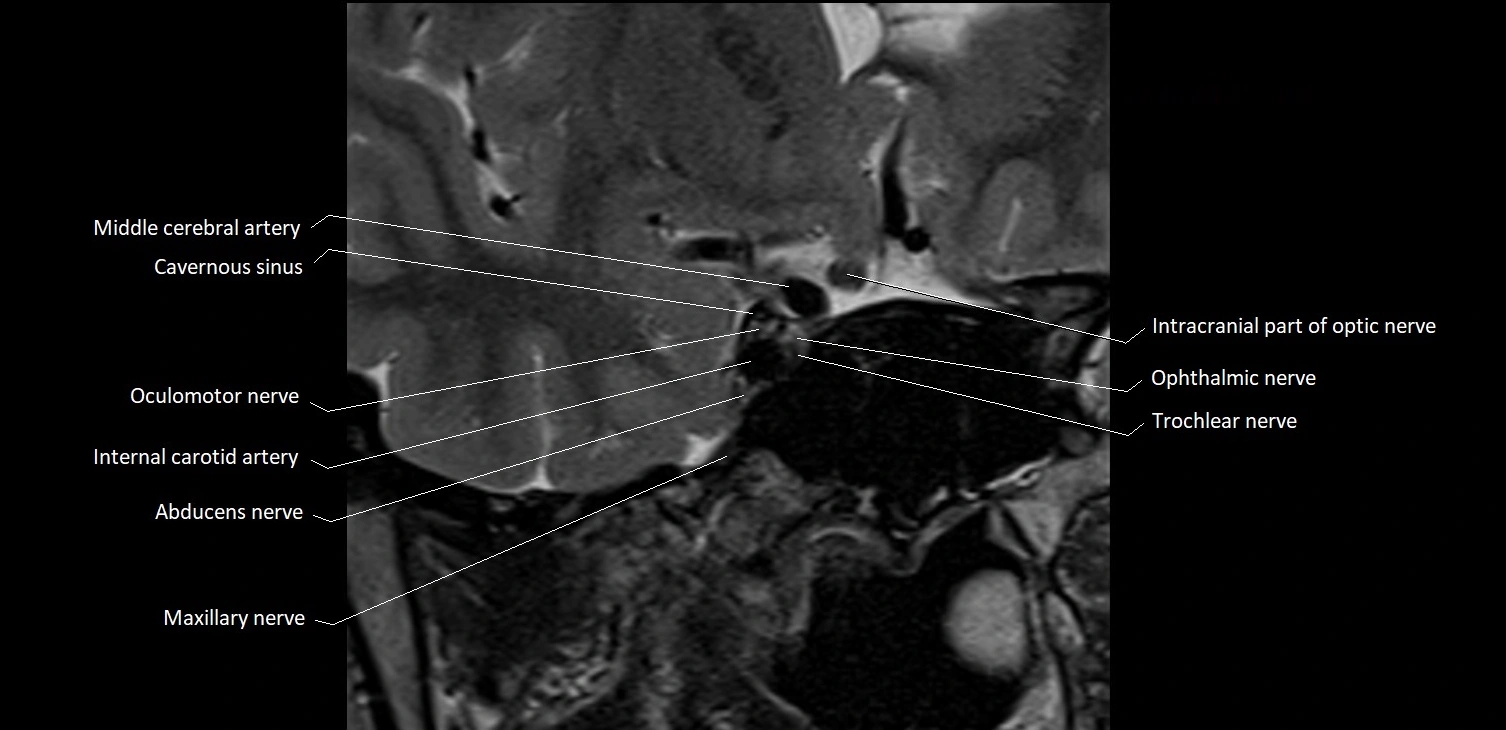

- Abducens nerve (Cranial nerve VI)

- Oculomotor Nerve (Cranial Nerve III)

- Trochlear nerve (Cranial nerve IV)

- Maxillary nerve

- Intracranial part of optic nerve